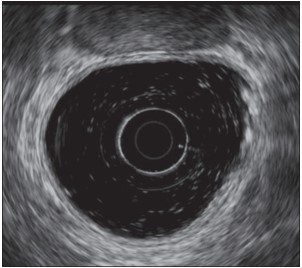

Anorectal Endoscopic Ultrasonography (EUS) is a minimally invasive procedure that combines endoscopy with ultrasound to obtain detailed images of the anorectal region. This technique is crucial for diagnosing various conditions such as anorectal abscesses, fistulas, and tumors.

EUS is highly effective in identifying anorectal abscesses and fistulas, conditions that can be challenging to diagnose with traditional imaging methods. It provides detailed images that help in determining the extent of the disease and planning the appropriate treatment.

For patients with anorectal tumors, EUS is invaluable in assessing the depth of tumor invasion and the involvement of surrounding structures. This information is critical for staging the tumor and planning the most effective treatment strategy.